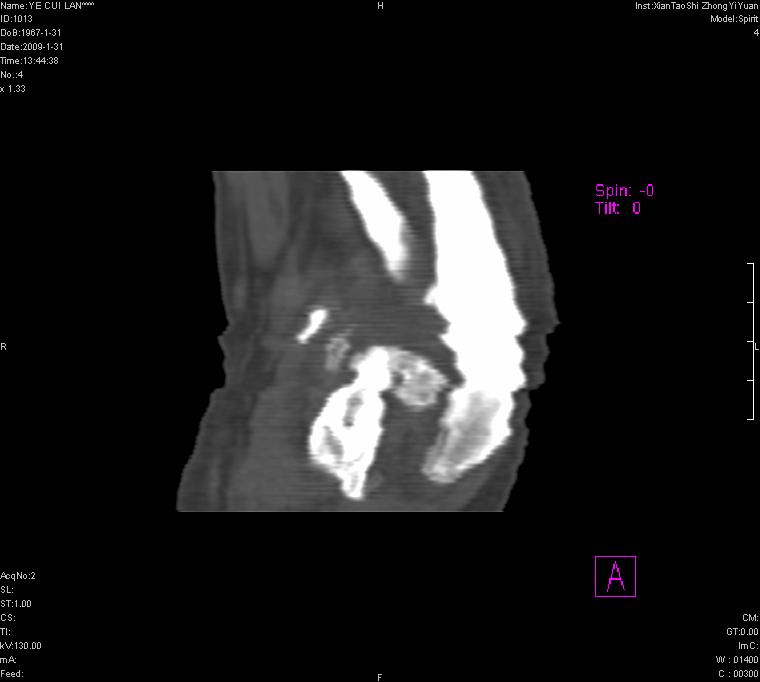

以下是引用王明发在2009-2-9 11:53:00的发言:[br]支持夏科氏关节,必要时行脊髓mri检查 [br]夏科氏关节是指由于某些神经系统疾病引起的关节病变,也被称为神经性关节炎。常见病因有脊髓痨、脊髓空洞症等。原发的神经病变可以造成关节深部感觉障碍,对于关节的震荡、磨损、挤压、劳倦不能察觉因而也不能自主地保护和避免,而神经营养障碍又可使修复能力低下,使病人在无感觉状态下造成了关节软骨的磨损和破坏,关节囊和韧带松弛无力,易形成关节脱位和连枷关节。关节面的破坏和骨赘的脱落变成关节内游离体。关节外形饱满肿胀,内有出血和渗出。这种病早期并无疼痛,不易被病人重视,仅表现为关节肿胀、无力、活动过度、动摇不稳。关节肿胀、无痛、活动范围超常是本病的重要特征。x光片可见有关节骨端广泛破坏、硬化或呈奇异形态,骨赘形成,关节间隙不规则或增宽,周围软组织钙化、关节内游离体、骨碎片等。结合x光片及临床症状,病人又有神经系统原发病症,即可确诊

以下是引用hhcckk在2009-2-9 14:31:00的发言:[br]夏科关节的六大表现[br]1.关节软组织肿胀。[br]2.关节的脱位与半脱位。[br]3.关节内的游离体。[br]4.关节面硬化,新骨形成。[br]5.骨质萎缩与破坏。[br]6.关节结构的紊乱。[br]加上患者无明显疼痛,诊断的把握性比较大